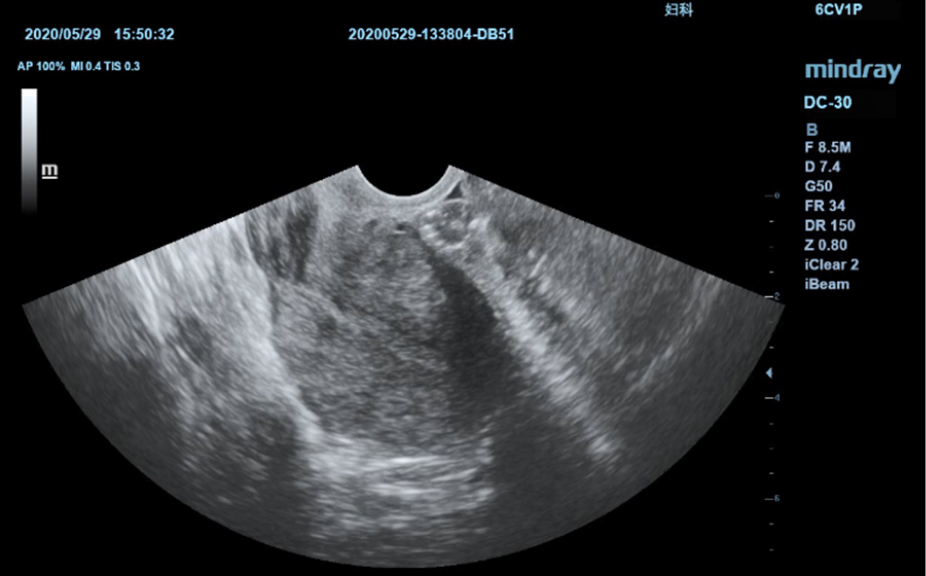

?ematik ve ultrason resimleri dahil, normal anatomik g?sterimler.

Standart ultrasonogram?n, ilgilenilen b?lge ĂŒzerinde g?rsel rehberlik sa?layan yan

g?rĂŒnĂŒmĂŒ.

Standart ultrason g?rĂŒntĂŒleri

3

Referans i?in ger?ek zamanl? tarama kar??la?t?rmas?.